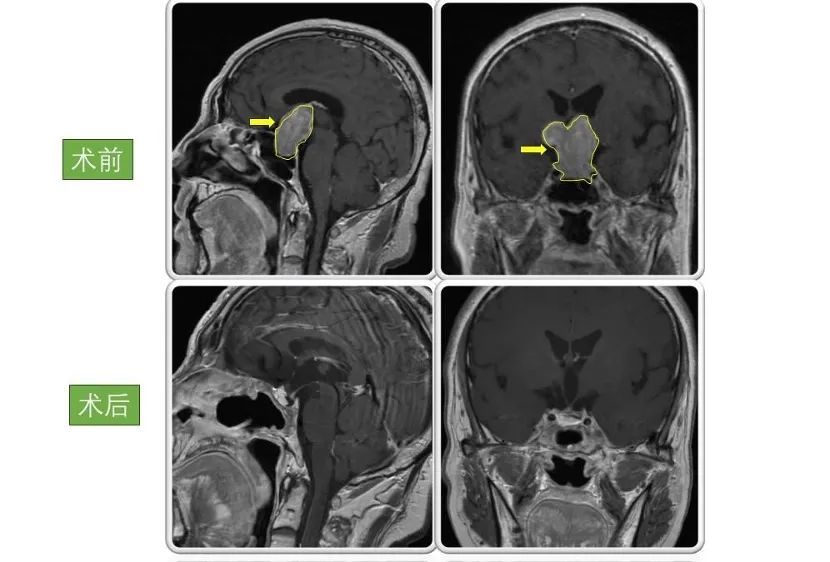

患者2

男性,66岁,因“双眼视物模糊4年,头晕伴恶心呕吐半个月”。入院检查显示巨大垂体腺瘤,大小为4.5×3.5×3cm。

术后患者视力好转,恶心呕吐症状消失。病情稳定后出院,现恢复良好,定期复查。